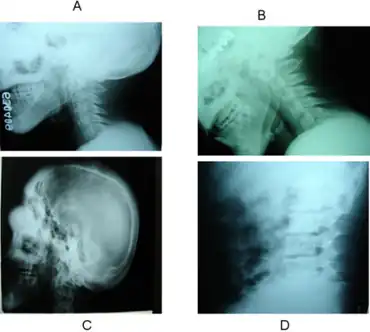

| Leontiasis ossea and cervical cord contusion as rare complications of Polyostotic fibrous dysplasia- a,b)Hypertrophy of posterior elements c)diffuse cortical thickening on lateral skull d) diffuse thickening of lumbar vertebrae. | |